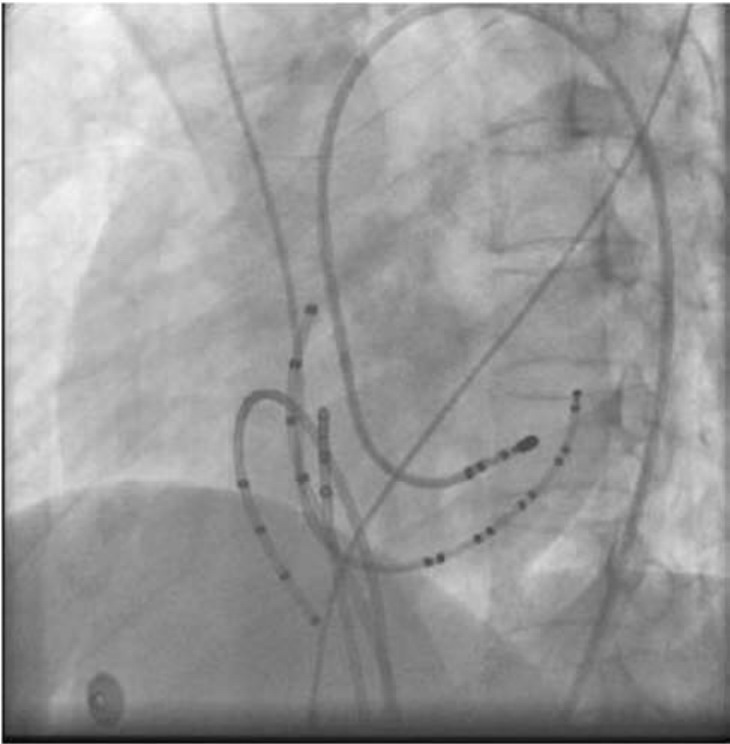

图64-12 房室结折返性心动过速

高右心房刺激S1s2=500/310ms跳跃诱发心动过速,符合AVNRT的腔内图特点与三尖瓣环间较难保持良好接触。

射频功率:一般采用温度控制消融,预设温度为55~60℃。有人认为,非温度控制消融在AVNRT的消融中更安全。放电过程中严密监测阻抗和心律,放电后出现缓慢的交界性心律视为消融有效(图64-12)。

X线靶点见下图

img1697

RAO30°

img1698

LAO45°